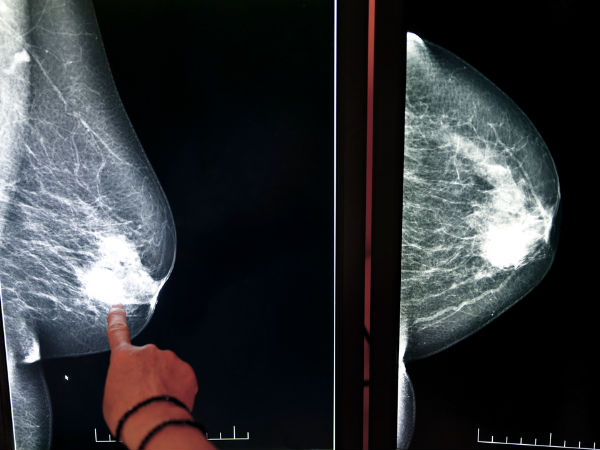

સગર્ભાવસ્થા અને બ્રેસ્ટ કૅંસરનાં ખતરા વચ્ચેનો સંબંધ

અભ્યાસો વડે જાણવા મળ્યું છે કે કોઈ મહિલાને બ્રેસ્ટ કૅંસર થવાનો ખતરો તેની ઓવરીઝ દ્વારા ઉત્પન્ન કરાતા હૉર્મોંસ સાથે સંકળાયેલો હોય છે. સગર્ભાવસ્થા બ્રેસ્ટ ફીડિંગની સીધી અસર બ્રેસ્ટની કોશિકાઓ પર પડે છે કે જેથી તેમનાં કેટલાક ફેરફાર આવે કે તે પરિપક્વ બની શકે તેમજ દૂધ બનાવી શકે. કેટલાક શોધકર્તાઓનું એવું માનવું છે કે આ પરિવર્તિત કોશિકાઓ જ કૅંસરની કોશિકાઓ બની જાય છે, જ્યારે અપરિવર્તિત કોશિકાઓનાં કૅંસરની કોશિકાઓમાં બદલવાનો ખતરો બહુ ઓછો હોય છે.

એવી મહિલાઓ કે જે બહુ ઓછી વયમાં માતા બની જાય છે, તેમનામાં બ્રેસ્ટ કૅંસર થવાનો ખતરો બહુ ઓછો હોય છે. એવી મહિલાઓ કે જેમણે 30 વર્ષની ઉંમર બાદ પ્રથમ બાળકને જન્મ આપ્યો છે, તેમનામાં બ્રેસ્ટ કૅંસરની શક્યતા તે મહિલાઓ કરતા વધુ હોય છે કે જેમણે ક્યારેય બાળકને જન્મ નથી આપ્યો.

મહિલાની પ્રથમ સગર્ભાવસ્થા બાદ બ્રેસ્ટ કૅંસર થવાની શક્યતા વધી જાય છે, પરંતુ તે ધીમે-ધીમે ઓછી થતી જાય છે તેમજ તે પછીની સગર્ભાવસ્થા પર તેની કોઈ અસર નથી પડતી.

મહિલાઓ દ્વારા બાળકને જન્મ આપવાની ઉંમર દર પાંચ વર્ષે વધી રહી છે કે જેના કારણે મહિલાઓને બ્રેસ્ટ કૅંસર થવાની શક્યતા 7 ટકાના દરે વધી રહી છે.